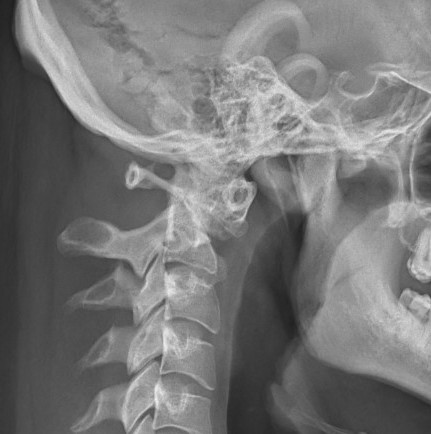

Xray

Atlanto-dens interval (ADI)

- > 5 mm indicates instability

Space available for Cord (SAC)

- posterior atlanto-dens interval (PADI)

- < 13 mm concerning

Increased ADI in patient with Down's syndrome

Flexion / Extension views

Down's syndrome flexion xray Down's syndrome extension xray